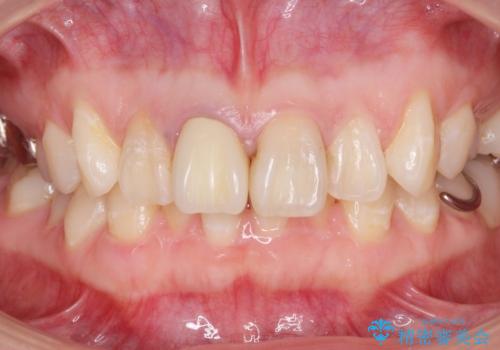

色のバランスもよく、適合も良い被せ物が入りました。

根管治療をした後、樹脂で埋めるだけで治療を終えてしまうと歯質と樹脂の隙間から細菌が入り込み、う蝕や根の感染の再発に繋がります。

適合の良い被せ物を入れることで再発リスクが低くなります。